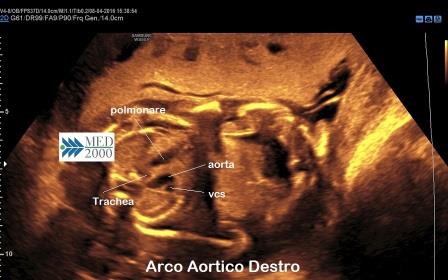

Arco Aortico Destro

L'Arco Aortico Destro è la più frequente anomalia dell'arco aortico (47% dei casi) associato nel 98% dei casi ad altre anomalie cardiache (Tetralogia di Fallot).

La diagnosi ecografica si basa sui seguenti reperti nella scansione 3VT:

- non si osserva la V

- l'aorta è destroposta rispetto alla trachea

- l'aorta destroposta determina un gap tra polmonare ed aorta

- l'aorta discendente è destroposta o mediana.

Quasi sempre tale anomalia è secondaria alla presenza di una cardiopatia congenita associata.